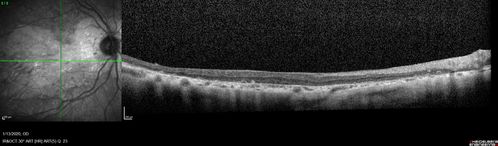

Severe Geographic Atrophy from Dry Age-Related Macular Degeneration

90 year old female with severe vision loss over the last few years.

VA 3/200 OD

1/200 OS